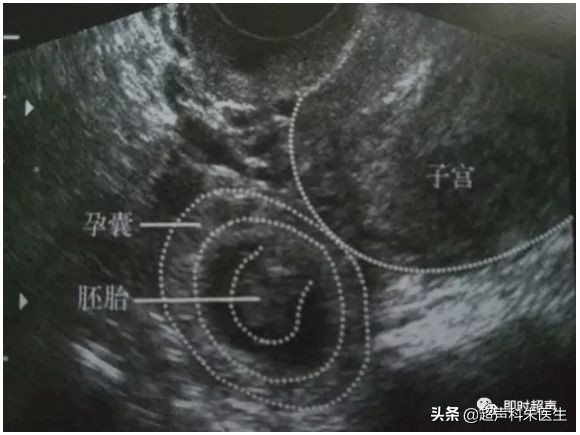

正常早孕及流产

正常早孕:宫腔内见到低回声的孕囊,其内见到卵黄囊,甚至是胚芽,可见原始心管搏动。

正常早孕

宫外孕